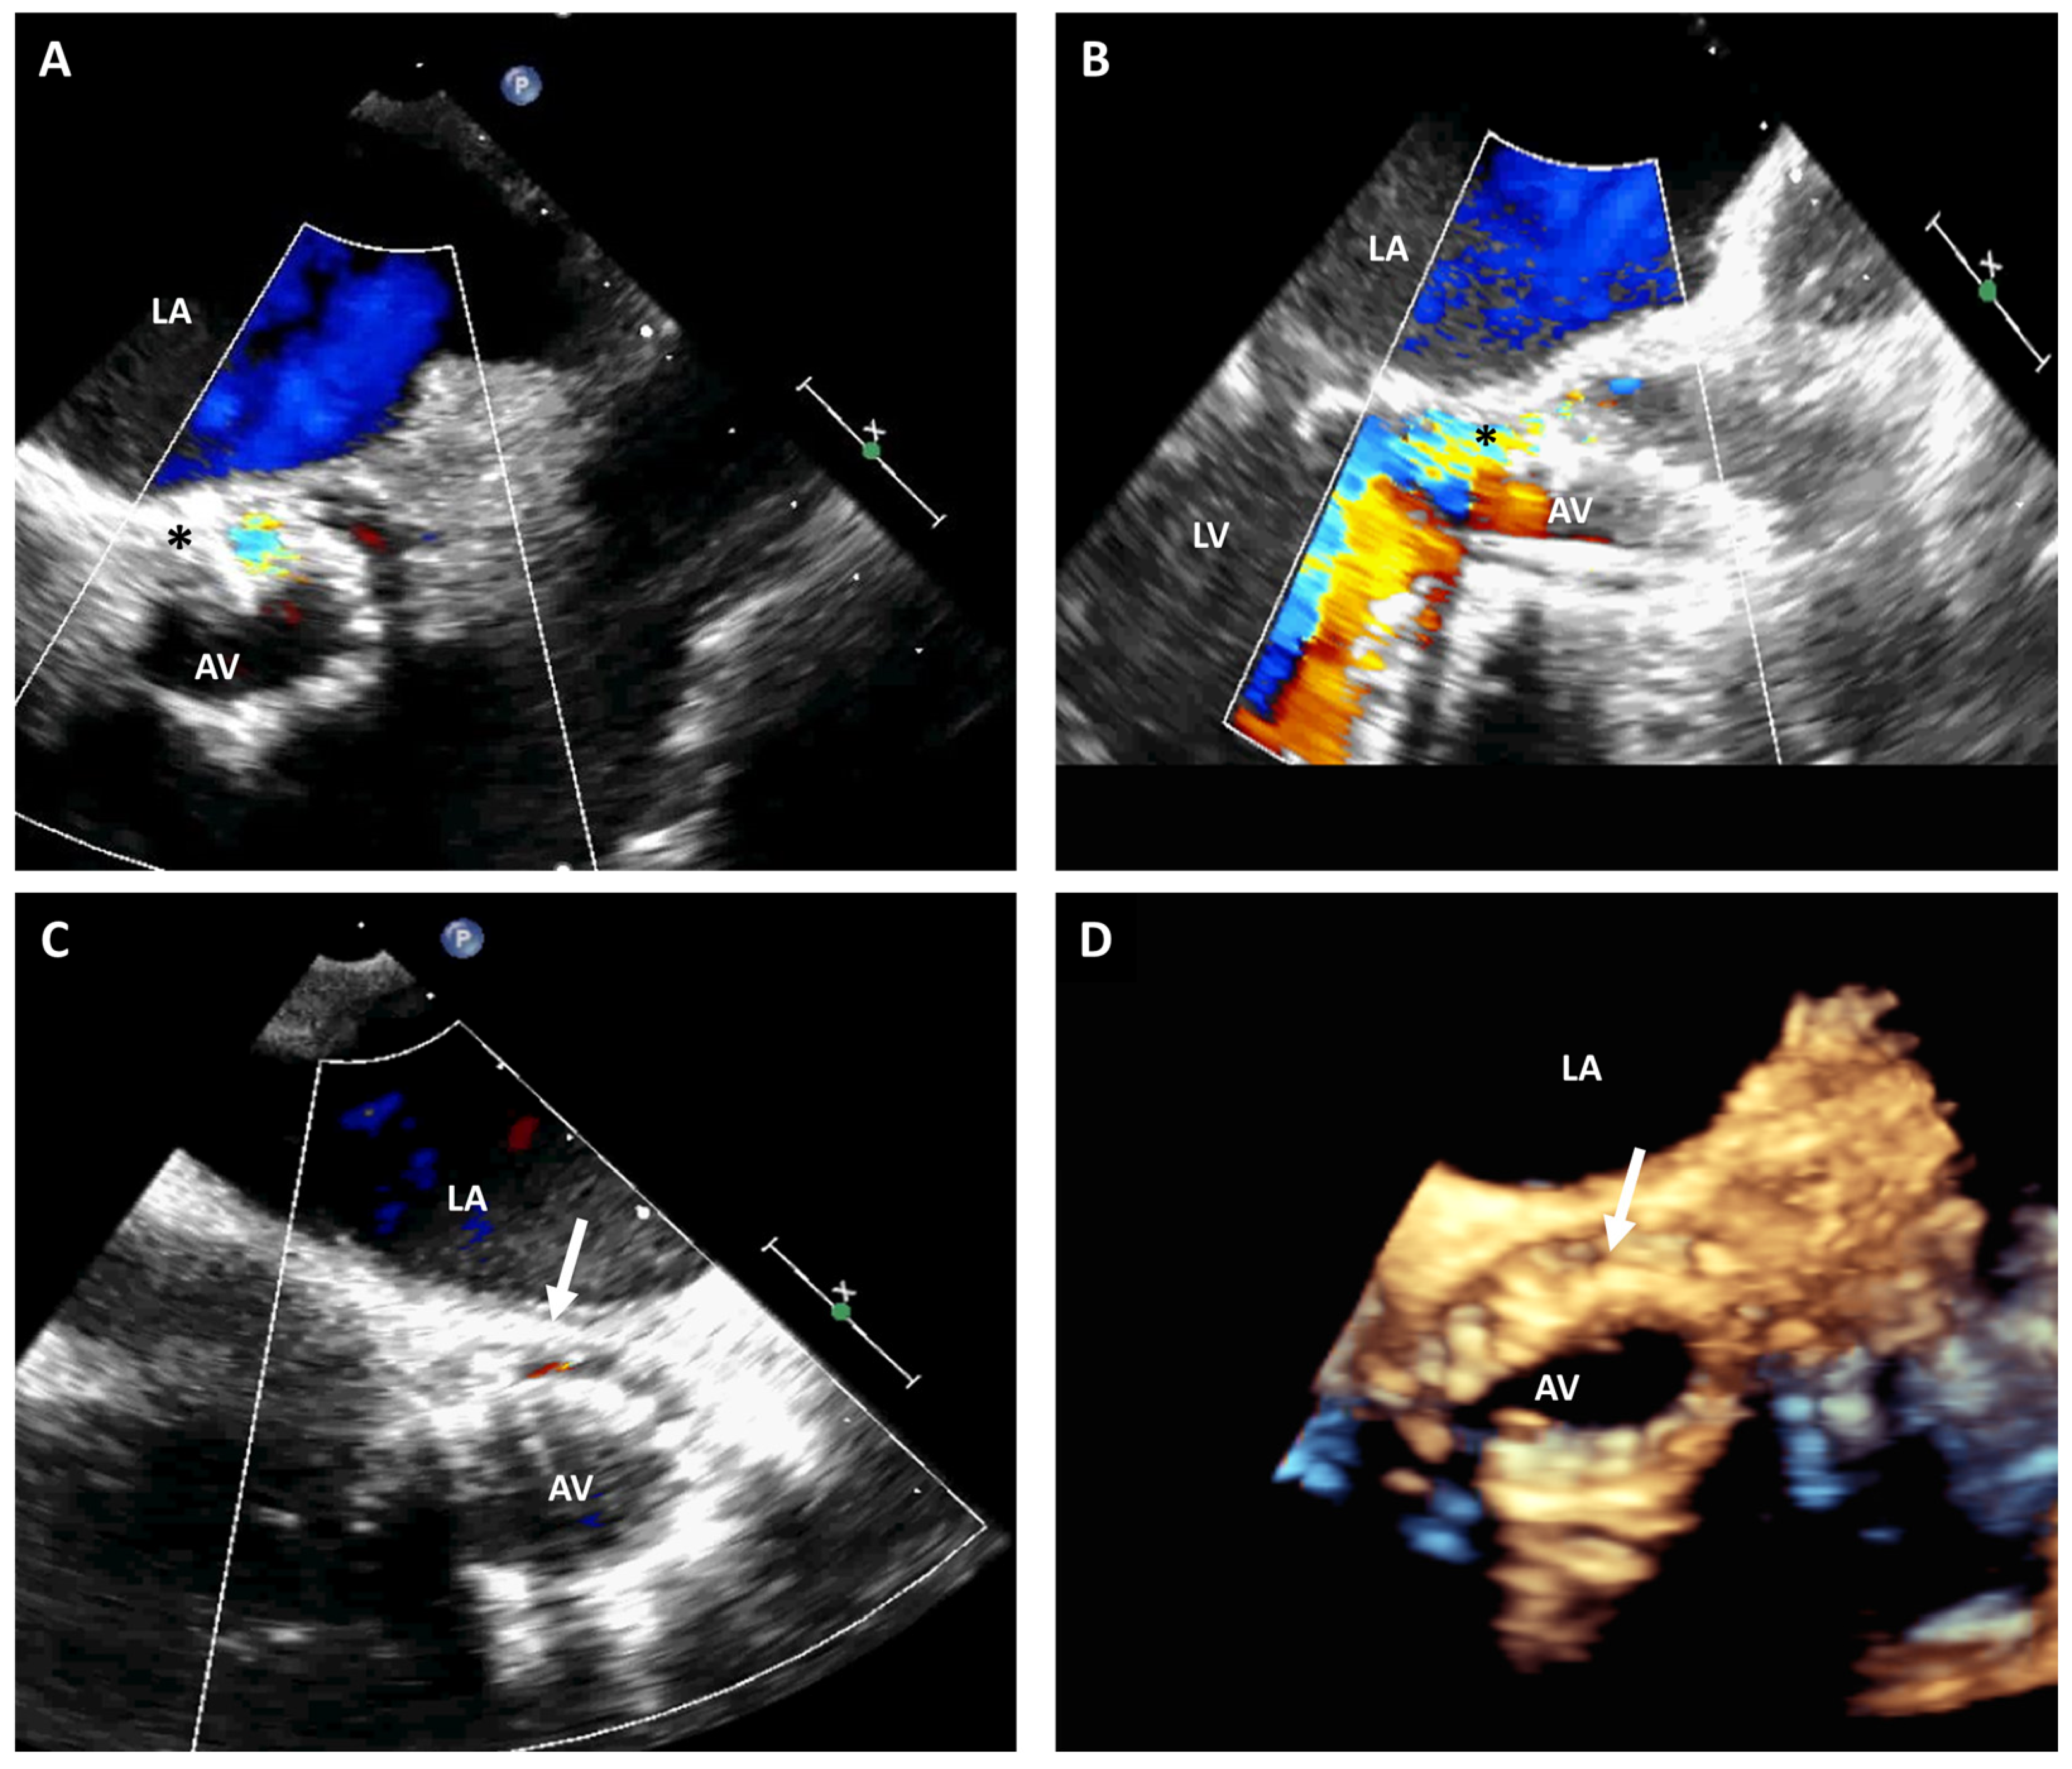

3.3. Paravalvular Leak Closure